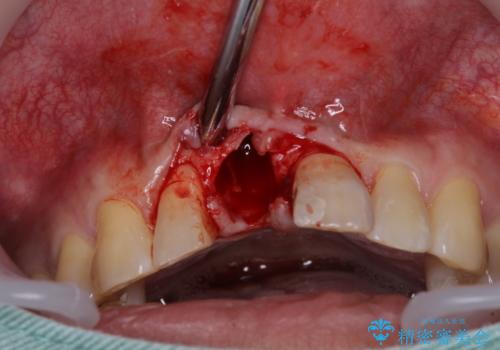

補綴治療としては、インプラントあるいはブリッジの2つがありますが、患者様と相談した結果、インプラントによる補綴治療を選択することとなりました。

咬合力が非常に強いため、インプラントにも過度な力の負担が発生する恐れがあります。

長期間安定して使用いただくために、睡眠時のマウスピースの装着による咬合力の分散が必要となります。

- 外科手術のため、術後に痛みや腫れ、違和感を伴います